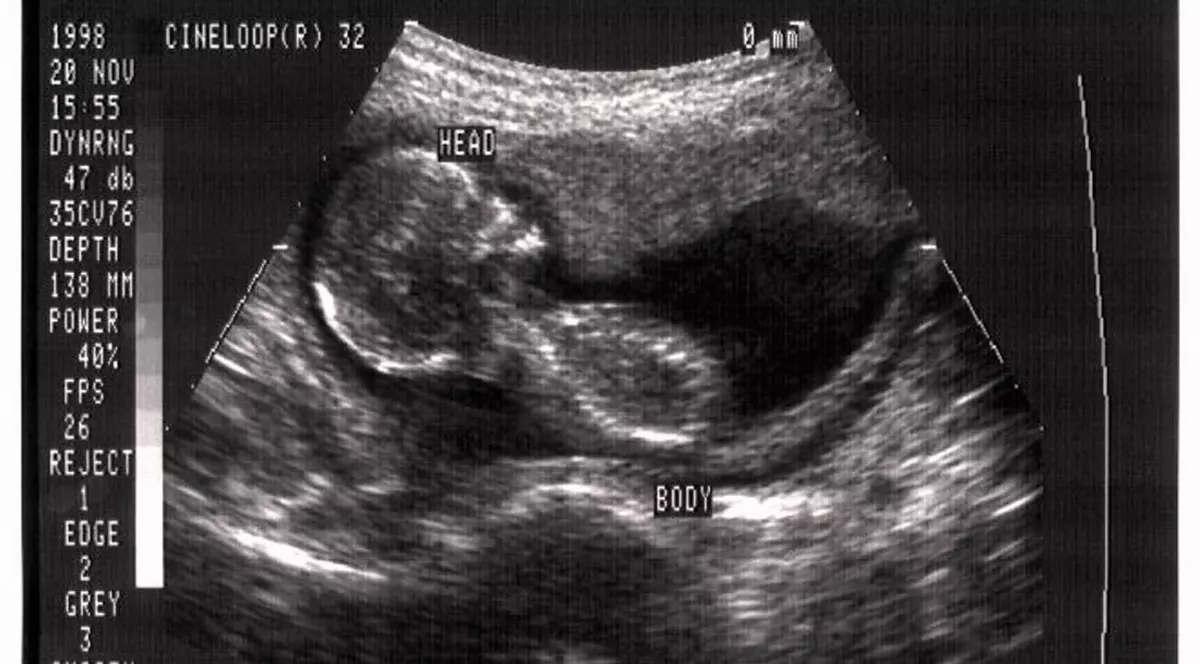

3. Cea mai lungă sarcină din lume i-a apaținut lui Jacqueline Haddock, care a avut o perioadă de gestație de 398 de zile. Aceasta a adus pe lume o fetiță de doar un kilogram si 360 de grame.